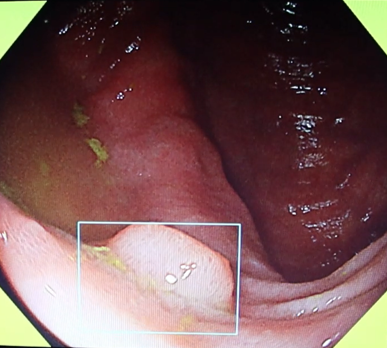

①病変をAIの目で瞬時に捕捉

経験豊富な内視鏡専門医の目に加えて、疲れ知らずのAIが大腸病変を瞬時に捕捉し追いかけます。

②発見したポリープを白色光で診断

発見したポリープはまず白色光で評価し診断します